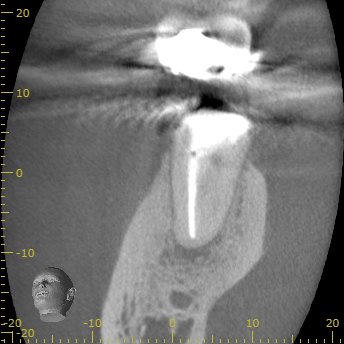

CBCT(2023.12.20)

MB

根切するには厳しい位置に#31のM根のApexはある。

穿通は必須である。

ML

MLには根尖病変と思しき透過像がそれほど顕著ではないが若干見える。

そして、生活歯髄療法の負の遺産がこの歯牙には発生している。

そう、

根管の石灰化

だ。

その歯に根尖病変ができている。

そして、Sinus tract。

この歯を根切することは容易であろうか?

といえば、

このCT画像が語っていることは、

頬側の皮質骨は相当厚いという臨床的事実だ。

それがApicoectomyを困難にしているのだろう。